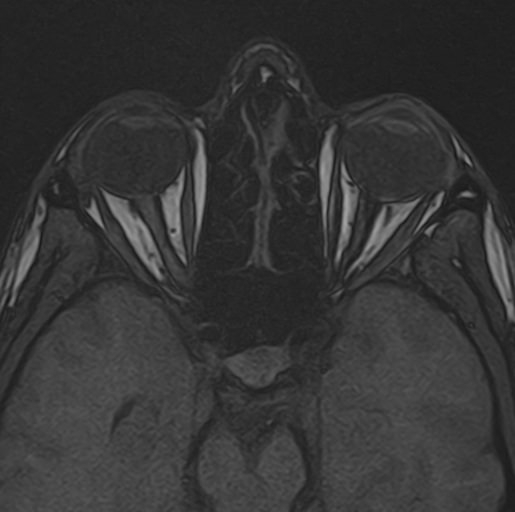

МРТ глазных орбит является современным способом диагностики патологии глазниц, в которых расположены глазные яблоки и их придатки (окружающая жировая клетчатка, зрительные нервы, слезные железы, мышцы глаза, связочный аппарат, кровеносные сосуды). МРТ орбит также позволяет получить детальную информацию о состоянии мягких тканей периорбитальных областей (тканей, окружающих глазницу).

Магнитно-резонансную томографию назначают при необходимости детального изучения мягкотканных структур глазниц. В результате исследования получают срезы анатомической области, на которых можно рассмотреть мельчайшие элементы. МРТ орбит обеспечивает визуализацию следующих структур:

• элементы глазного яблока, включая оболочки;

• периорбитальная клетчатка;

• мышечный аппарат;

• зрительный нерв;

• слезные железы.

Ангиорежим позволяет изучить сосуды глаза (глазная артерия и вены сетчатки).